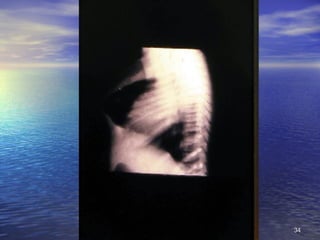

2. Signos Circunstanciales No se encuentran siempre, sino que están condicionados a causas ambientales o ecológicas, no específicas: alteraciones de la piel y faneras, lesiones oculares, de lengua, óseas, de músculos y ligamentos, de aparato digestivo, alteraciones hematológicas, neurológicas, edema

2. Signos CircunstancialesNo se encuentran siempre, sino que están condicionados a causas ambientales o ecológicas, no específicas: alteraciones de la piel y faneras, lesiones oculares, de lengua, óseas, de músculos y ligamentos, de aparato digestivo, alteraciones hematológicas, neurológicas, edema